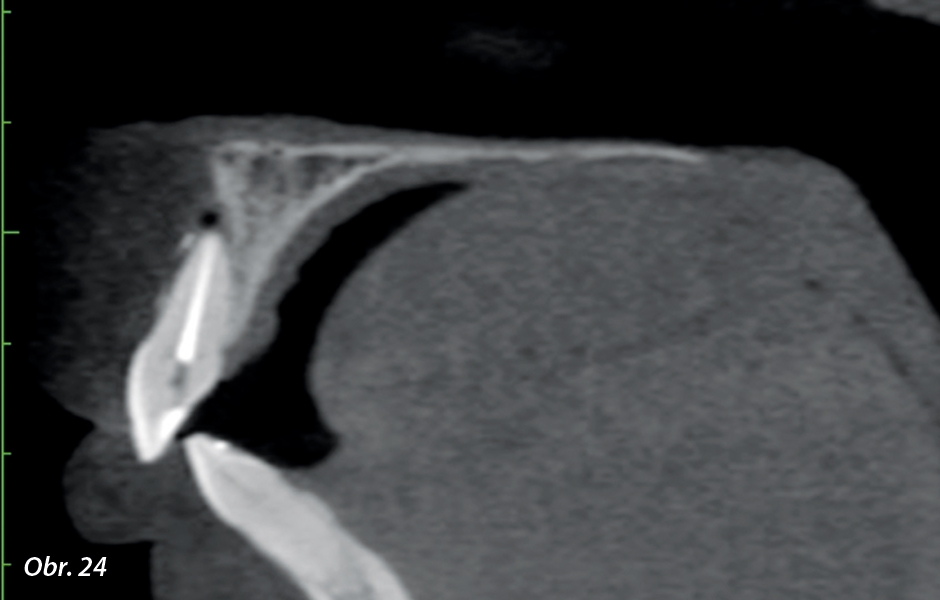

PCO většinou postihuje frontální zuby mladých dospělých a může způsobit kompletní nebo částečnou obliteraci kořenového kanálku. Začíná v korunce zužováním pulpální dutiny a šíří se apikálně, je doprovázena postupným zmenšováním prostoru kořenového kanálku.5, 6 Kompletní radiografická obliterace pulpálního prostoru nutně neznamená absenci prostoru v kořenovém kanálku. Ve skutečnosti je u většiny z těchto případů přítomna pulpální tkáň, ale citlivost radiologických vyšetření je příliš nízká na to, aby nám umožnila vizualizovat průběh kořenového kanálku.1

V dnešní době zvýšilo používání nových technologií předvídatelnost léčby kalcifikovaných zubů. Zubní operační mikroskop zlepšuje viditelnost pulpální kavity a používání ultrazvukových koncovek umožňuje bezpečnou práci ve větší hloubce systému kořenových kanálků, což může pomoci v identifikaci kořenového kanálku. Počítačová tomografie s kuželovitým paprskem (CBCT) u PCO případů mimořádně pomáhá tím, že umožňuje prohlížení 3D obrázků bez překrývajících struktur, což usnadňuje identifikaci kanálků a jejich anatomie, stupně obstrukce a rozměrů.2, 6, 11

Existuje nový klinický přístup k zubu s PCO nazvaný „navigovaná endodoncie“. Tato technika kombinuje použití naváděcí šablony s CBCT, což usnadňuje nalezení těžce kalcifikovaných kořenových kanálků.2, 4, 6, 8, 11 Tvar šablony je vytvořen na základě anatomie kořenového kanálku a architektury zubu a okolních struktur získaných z CBCT skenů a otiskem nebo intraorálním skenováním.12 Software asociovaný s CBCT daty a 3D intraorálním skenováním, jako je coDiagnostiX (DentalWings) nebo Simplant (Dentsply Sirona), se využívá pro virtuální plánování přístupové kavity.7, 12 Poté je vyrobena 3D virtuální šablona k získání fyzického modelu endodontické šablony, která zajistí orientaci preparačního nástroje do kalcifikovaného kořenového kanálku.7, 12